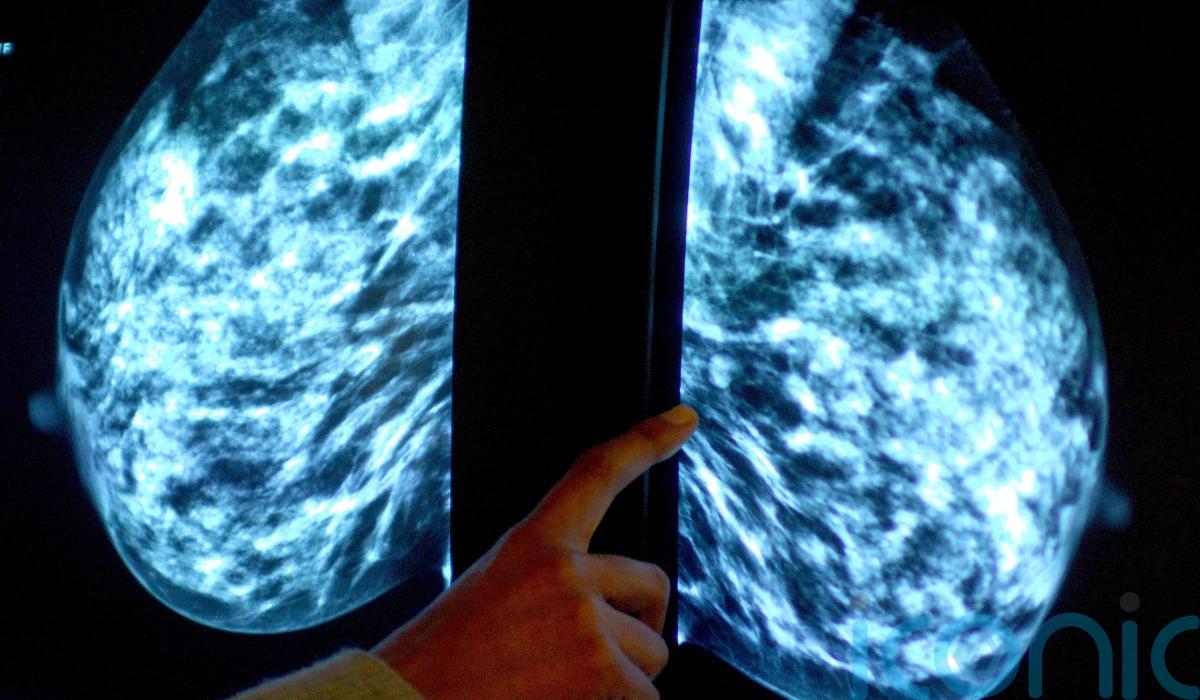

Immune cell discovery ‘could lead to personalised treatment for breast cancer’

Scientists have found that some immune cells hunt down cancer in the body, a discovery that could lead to personalised treatments for advanced breast cancer.

The study identified features of cells called immune B cells which make them successful at targeting tumours, including when cancer has spread to a different part of the body.

Researchers have developed a tool to identify these anti-cancer cells which could lead to improved, personalised immunotherapies, they say.